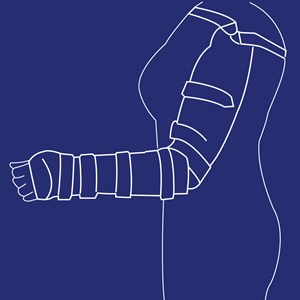

Helarmsortose (SEWHO)

Type: pdf

Størrelse: 861 KB